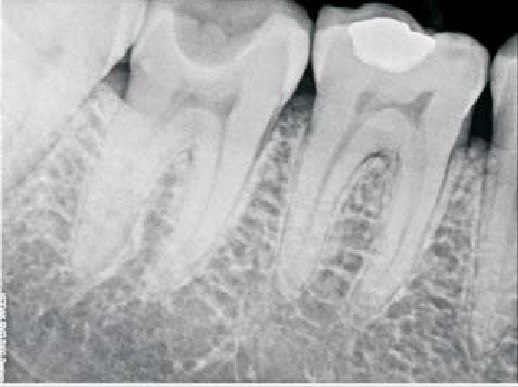

36 / 50

36. What is the caries level of the distal surface of the tooth # 3.4 and mesial surface of the tooth # 3.5 respectively?

37 / 50

37. What is the caries level of distal of the tooth # 3.6?